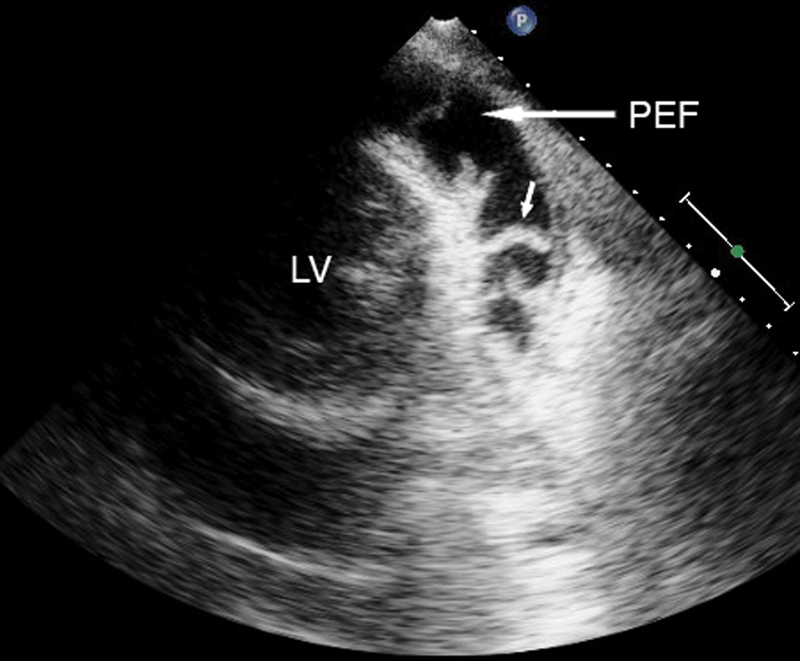

فحوصات تشخيصية لبعض امراض القلب والشرايين التاجية